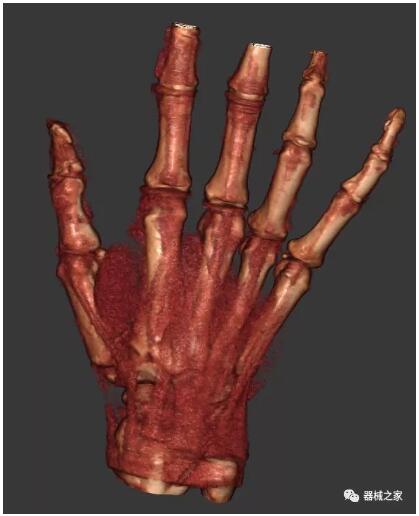

以上介紹的CT均來自國外同一家公司,這些CT均配置了可視化軟件,可以進(jìn)行切片、3D重建以及大型CT附帶的所有典型的操作功能。

以下是這些“特立獨(dú)行”的CT所拍出來的圖像: